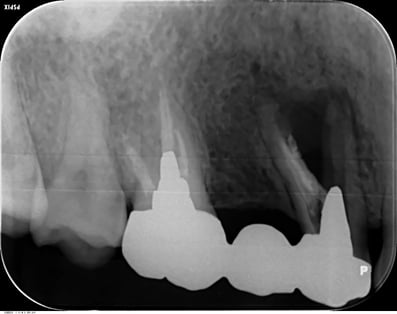

大臼歯の近心根の遠心壁に大きな穿孔が生じていた症例です。体格の良い男性でした。CTによる読影でも、大きな透過像が確認されます。この症例は、チタンメッシュとスーパーボンドを用いて修復しました。

CTでは、頬側の骨が破壊されていないことがわかります。おそらく、治療できるギリギリの時期であったかもしれません。穿孔封鎖後、遠心根も近心根も清掃拡大し、バイオセラミックスにて根尖を封鎖し、グラスファイバーにて築造。上部構造は、メタルのクッション性、メタルマージンの補綴物によるフェルール(帯環)効果を考え、P.F.M.C.としました。

外科的な治療は、第一大臼歯であっても、患者さん個々の頬粘膜の開き具合などのよって可能な場合と不可能な場合もあり、歯牙の部位で可否を決定するべきでないと思っていますし、体格の良い男性でしたが、外科的な処置にはかなり臆病だと感じましたので、非外科的に治療ができてよかったと思っています。

術後、7年経過していますが、問題なく機能しています。